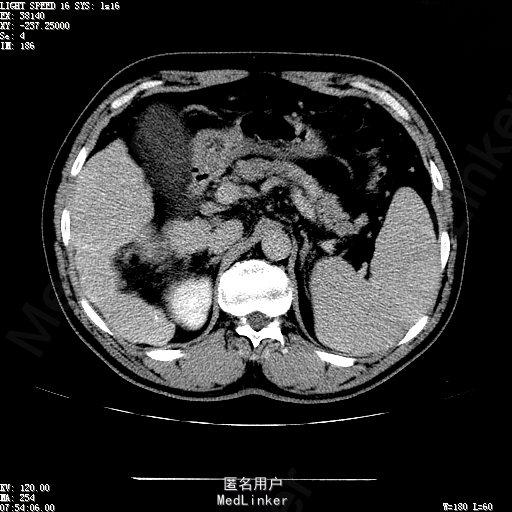

诊断:1、丙肝肝硬化 代偿期;2、原发性肝癌 S5段、S6段 该患诊断明确,既往曾行TACE治疗肝癌,S5段、S6段近右肾上极2处碘油沉积明确,S5段者较大,约2.31cm。超声显示清晰,为防止癌灶复发,适合行射频消融治疗。